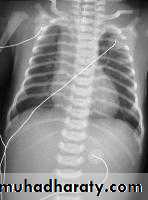

9- CXR shows widening of mediastinum.

10-Absence of fundal gas shadow.

LEFT: Dilated esophagus (arrows) appears as long, well-defined structure paralleling heart RIGHT: Dilated esophagus usually deviates to right. Narrowing (arrow) at hiatus.

LEFT: CT shows dilated esophagus (arrow) that led to esophagram.RIGHT: Esophagram shows narrowing (arrow) at level of hiatus.